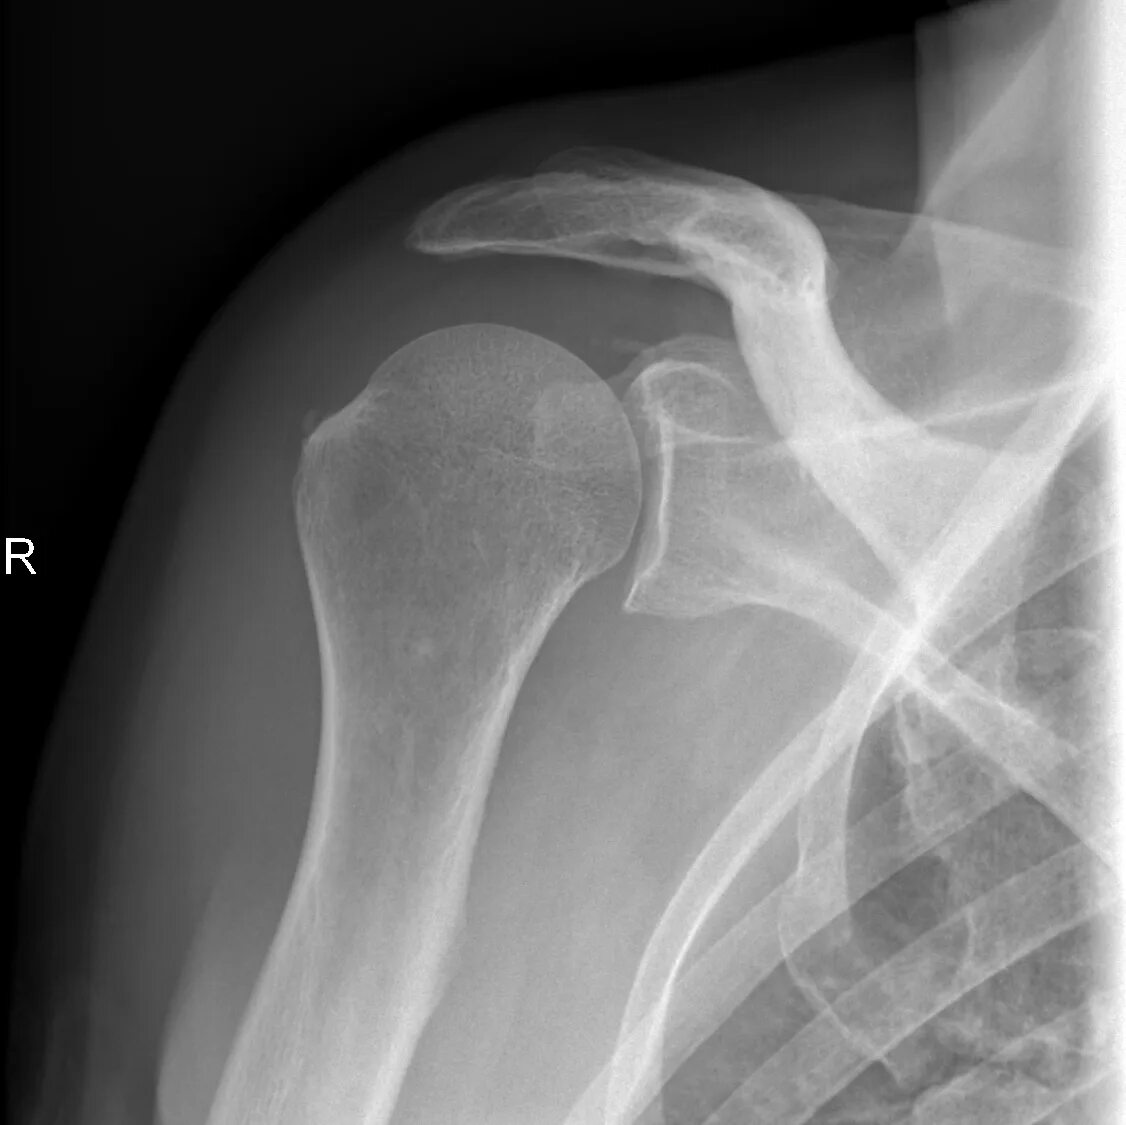

Перелом большого бугорка реабилитация